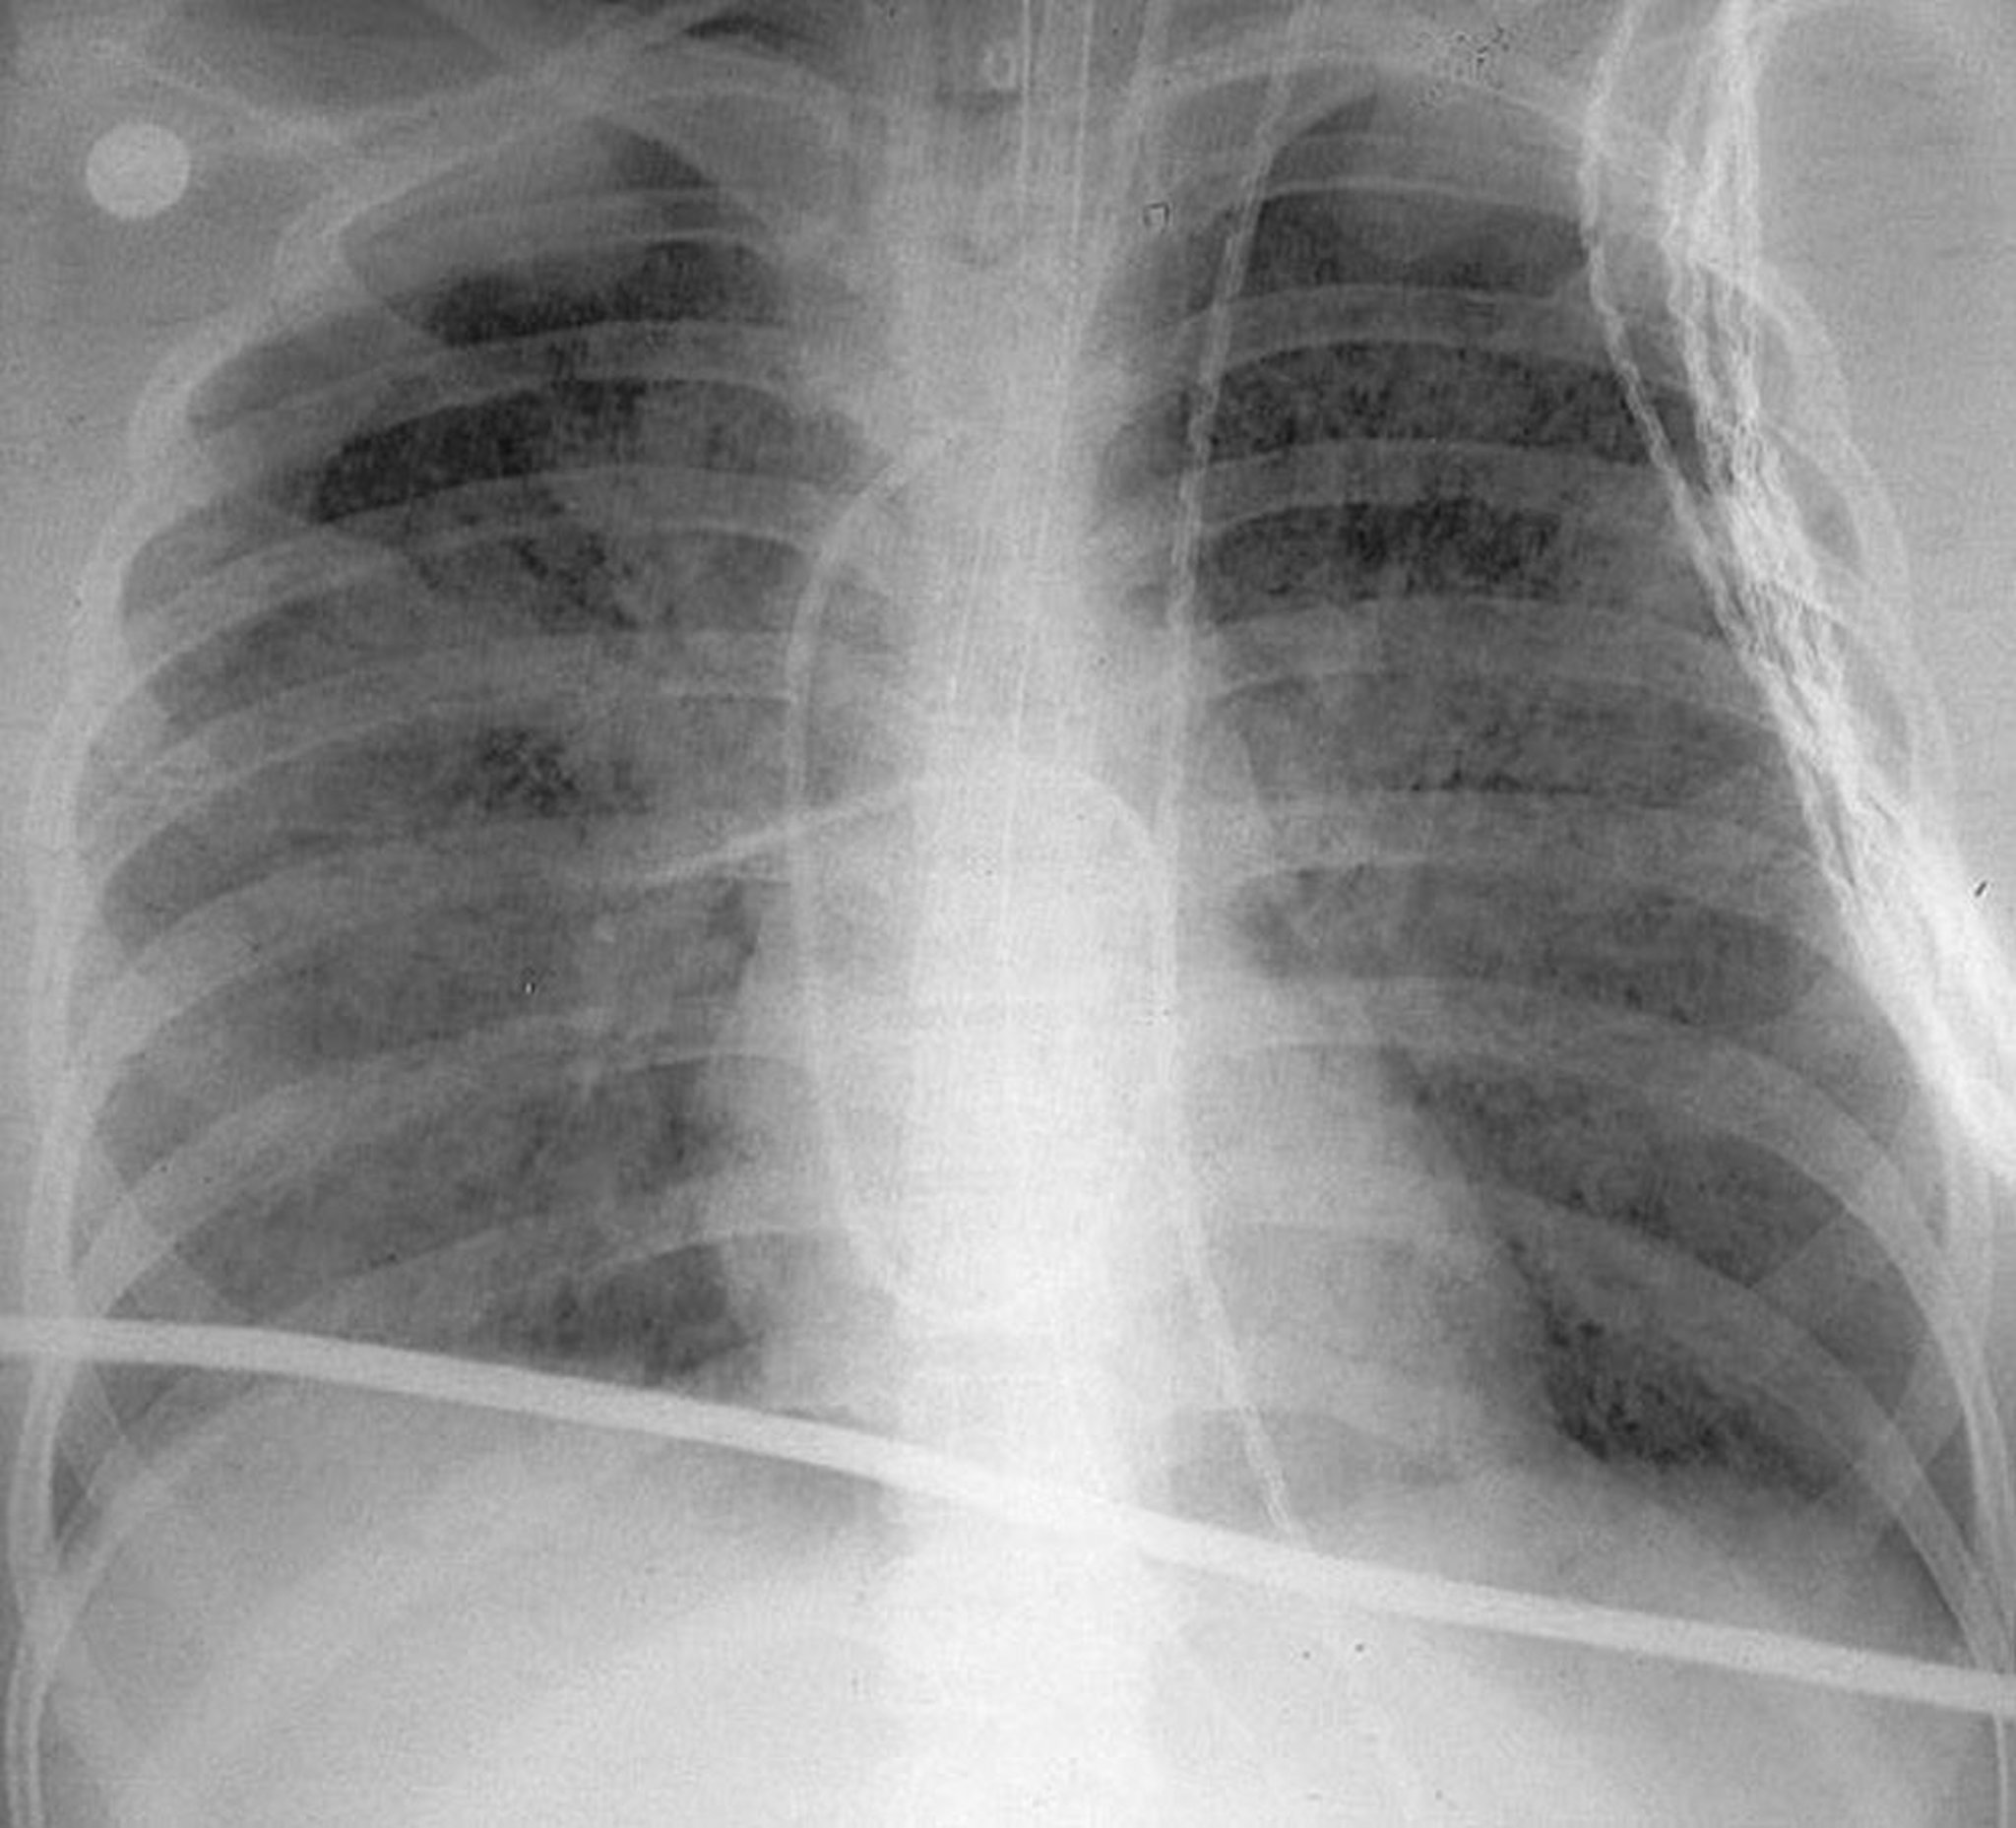

Esta radiografía de tórax de pie muestra opacidades bilaterales difusas características de un síndrome de dificultad respiratoria aguda (SDRA).

By permission of the publisher. De Herdegen J, Bone R. In Atlas of Infectious Diseases: Pleuropulmonary and Bronchial Infections. Edited by G Mandell (series editor) and MS Simberkoff. Philadelphia, Current Medicine, 1996.